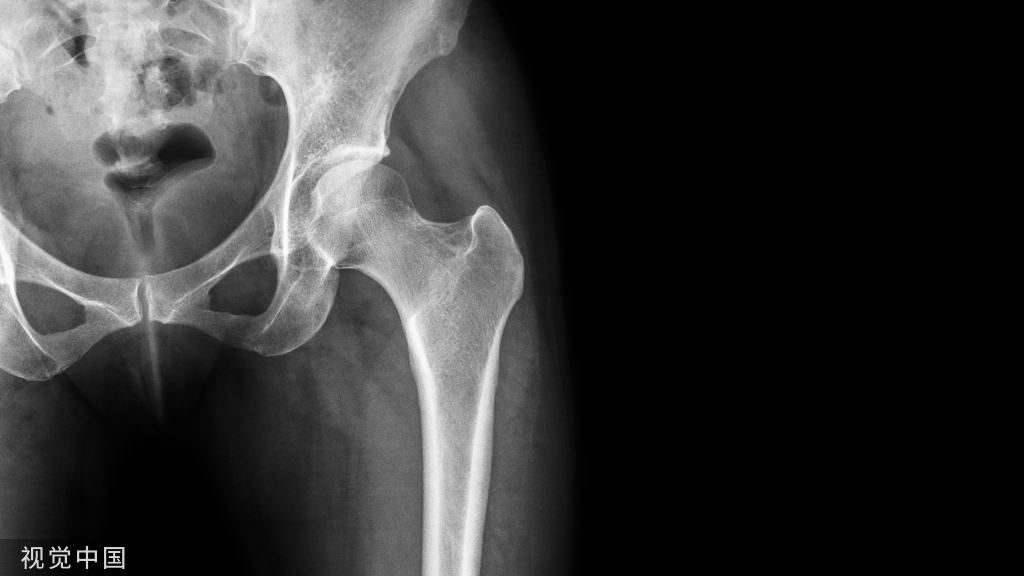

先别急着决定,看看CT再说:

这个面积,超出了一般微创植骨工具所能及的范围;若开放植骨,则外侧柱会自然而然成为“天然死角”,术后拍片估计要打脸。

换?看上去又不是那么急迫——关节面好好滴呢!

而且才34岁!

比较进退两难的境地。